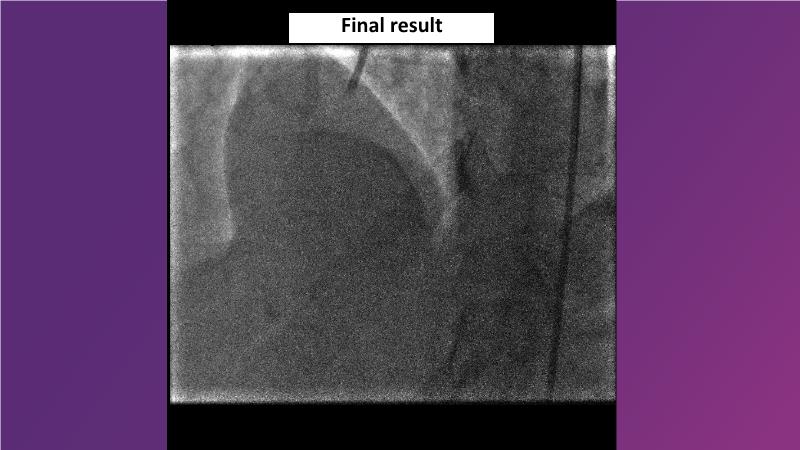

Sirolimus-coated balloon: exploring the case- and clinical-based evidences

Browse this EuroPCR 2024 session to explore the safety and efficacy of sirolimus-coated balloons from pre-clinical data, review MagicTouch data from real-world populations with case-based examples, and learn about the MagicTouch sirolimus-coated balloon clinical programs. Discover insights and takeaways from the significance of the EASTBOURNE subgroups, and analyze the challenges and opportunities in PCI for diabetic patients.